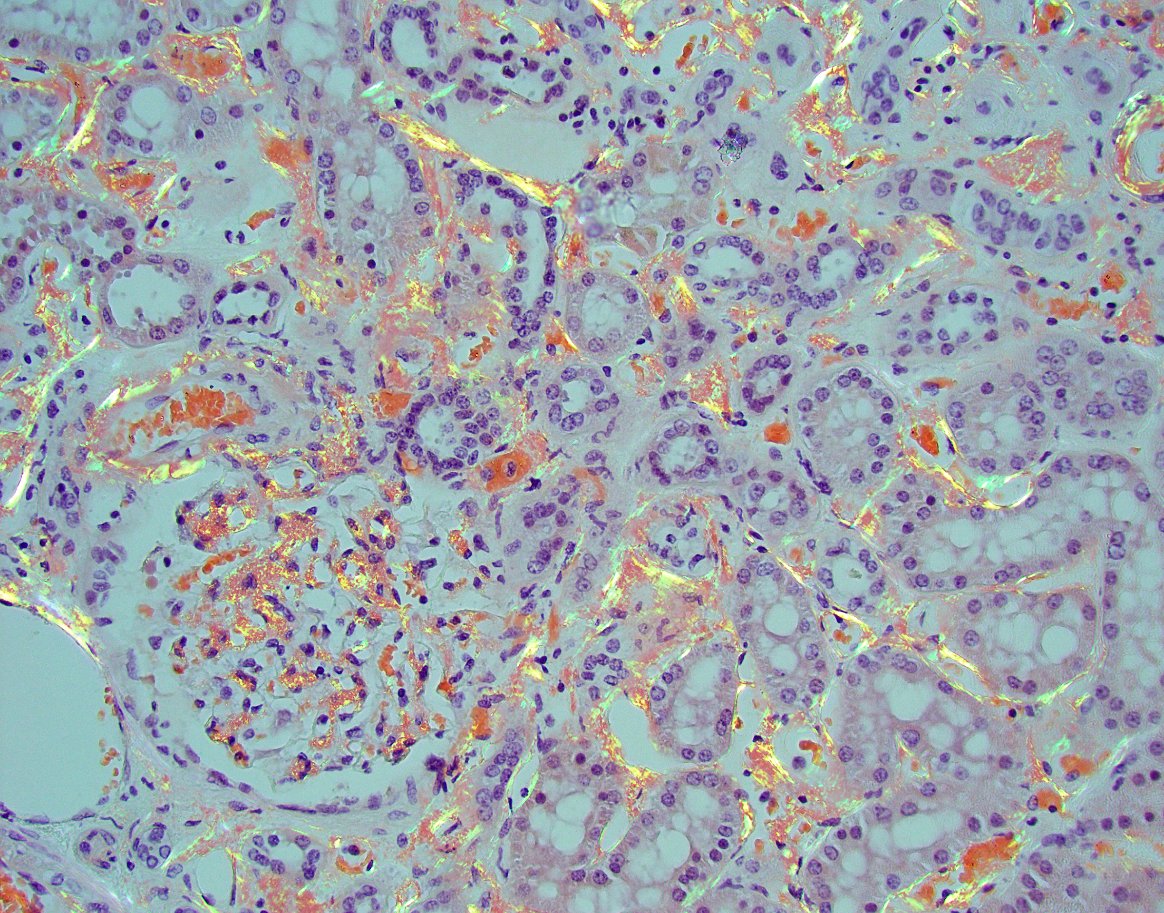

"The Banff 2024 Kidney Meeting Report: Rejection as a spectrum of phenotypes and focus on differential diagnostic reasoning," Naesens et al.